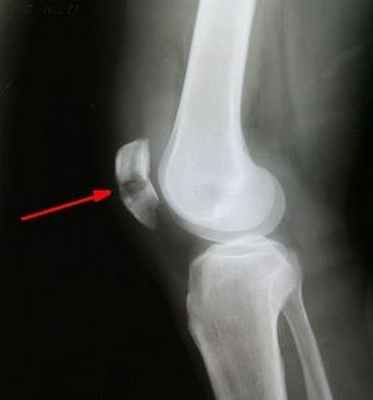

Диагностика перелома надколенника

Диагноз перелома надколенника устанавливается в ходе консультации травматолога на основании характерной клинической картины и данных рентгенографического исследования. Дополнительно проводится МРТ коленного сустава и УЗИ для выявления повреждений сухожилий и связок. Гемартроз подтверждает диагностическая пункция сустава. Перелом надколенника дифференцируют от разрыва собственной связки надколенника, разрыва сухожилия четырехглавой мышцы, травматического артрита и препателлярного бурсита. Во всех указанных случаях отсутствует щель между отломками, выявляется баллотирование коленной чашечки, надколенник смещается полностью.

В отдельных случаях перелом надколенника приходится дифференцировать с аномалией развития коленной чашечки – разделенным надколенником (patella partita - надколенник дольчатый - аномалия развития: надколенник, состоящий из двух или трех фрагментов). В отличие от перелома надколенника при patella partita в анамнезе отсутствует травма, нет резких болей, щель между костными фрагментами ровная, закругленная. В зависимости от количества частей, надколенник называется patella bipartita, tripartita, quadripartita, multipartita. Данная аномалия, как правило, выявляется с двух сторон.

- рентгенография в прямой и боковой проекции (выявление нарушения целостности кости)